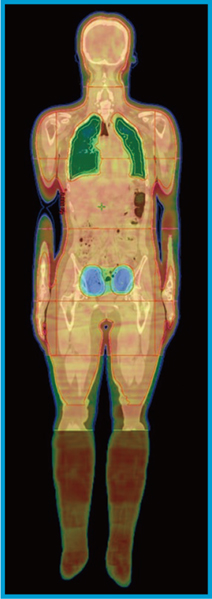

患者固定や治療計画方法は症例1と同様とした。本症例は,再生不良性貧血で若年女性でもあったため,卵巣線量低減を行った。計画CT撮影は,子宮の動きによる卵巣の位置移動を抑制するため排尿後に行った。卵巣周囲2cmを線量低減域としてPTVから切り取った。卵巣線量は0.4Gy/Frまで低減した3)(図3)。本症例ではTBI実施時,CBCTにて両側卵巣が線量低減域に確実に入っていることを確認することができた。

図3 症例2の線量分布図